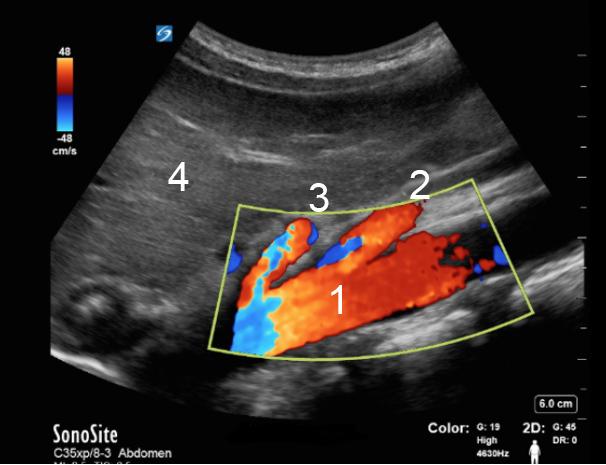

Aorta Color Sagittal Image

Aorta

Superior Mesenteric Artery (SMA)

Celiac Artery

Liver